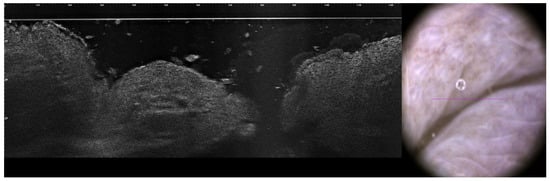

3.6.2. LC-OCT (Line-Scan Optical Coherence Tomography)

3.6.3. High-Frequency Ultrasound (HFUS)